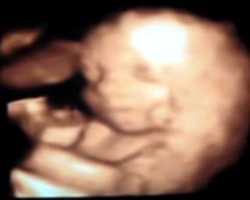

- ecografia 4D ajuta in reprezentarea imaginii ecografice spaţială a formelor aflate în volumul examinat ecografic, în timp real.

- ecografia fetală 4D ne prezinta imaginea corpului fătului aflat în uter cu mişcările pe care le are în momentul examinării.